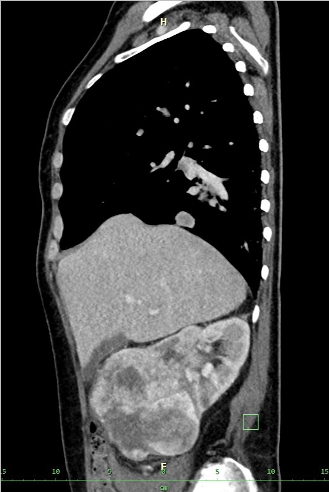

NO: 58letá žena, u níž byla na CT zjištěna objemná vaskularizovaná expanze pravé ledviny 10x12 cm bez trombózy, bez lymfadenopatie. Poté na CT zobrazeny četné plicní metastázy velikosti do 4 cm a metastáza na rozhraní acetabula a kosti kyčelní vpravo. Pod CT kontrolou provedena biopsie nádoru ledviny. Jedná se o tumor pravé ledviny (12 cm) cT2b cN0cM1 (plíce, pravá kyčel).

/ Obr. č. 1-5: CT hrudníku, břicha a pánve, patrná expanze pravé ledviny, plicní metastázy, lytická metastáza v pravé kyčelní kosti.